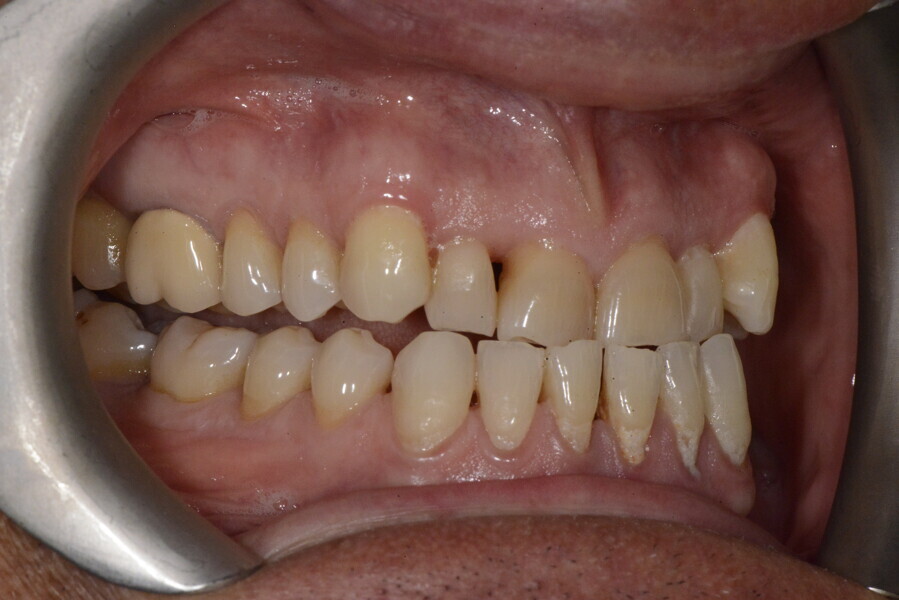

The 58-year-old patient wished to improve his oral aesthetics and function, complaining of mobility of the posterior teeth and wear of the anterior teeth. After data collection, a very complex situation was identified (Figs. 11–13):

1. severe periodontitis with poor prognosis of some teeth;

2. anterior crossbite;

3. severe wear mainly of the anterior teeth and compensatory eruption;38

4. atypical swallowing and lower posture of the tongue at rest;

5. masticatory dysfunction during the mastication test; and

6. no significant signs of temporomandibular disorder.